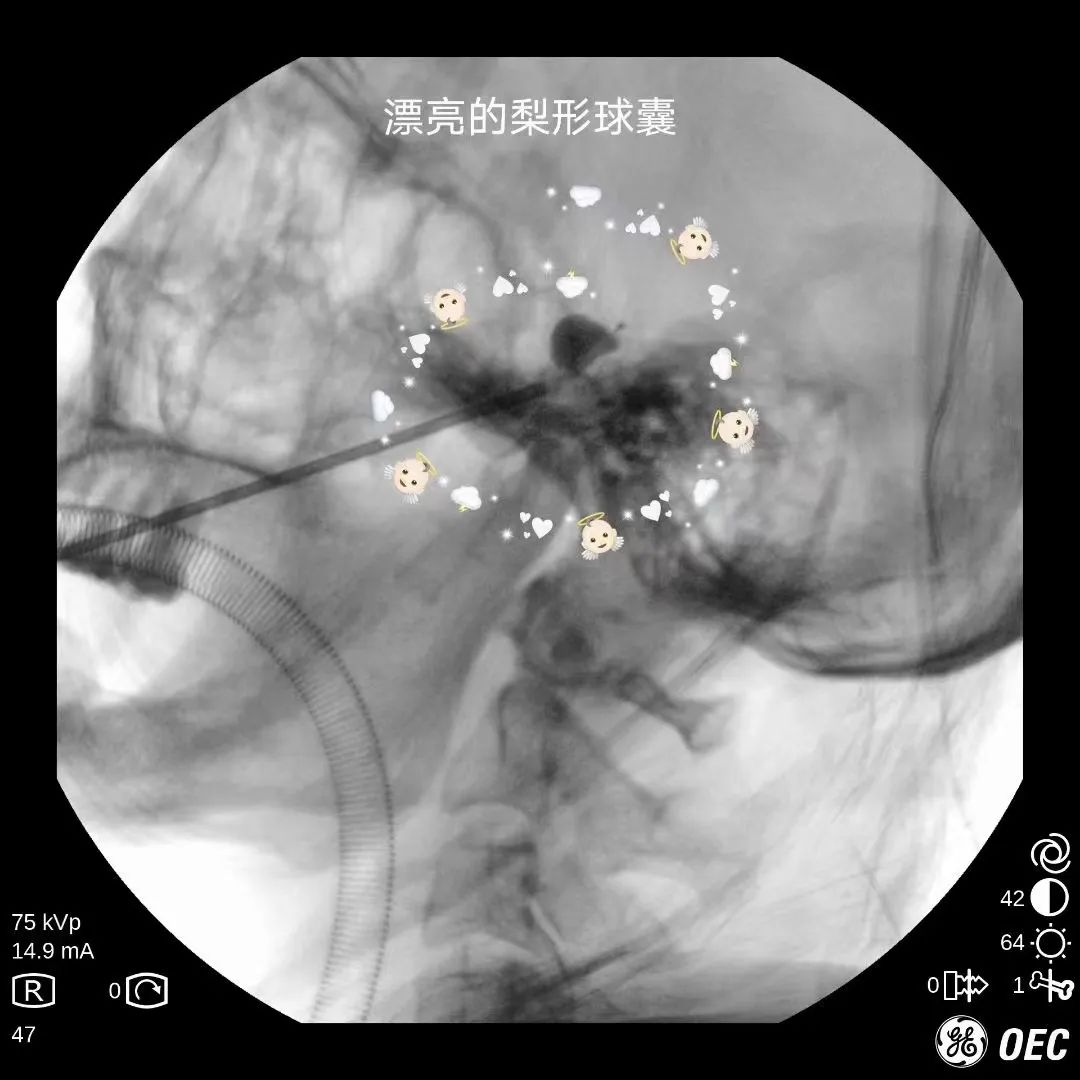

经皮穿刺三叉神经半月节球囊压迫术 :手术在C型臂及超声引导下成功穿刺至颅底孔隙,利用球囊的压力对三叉神经的关键部位进行压力治疗,使痛觉信号无法上传到大脑从而达到止痛的目的。

这种手术方法 无手术切口、安全有效、并发症少、患者恢复快, 迅速得到业界追捧,但因对术者技巧、手术器械、手术设备要求较高,开展起来有一定难度。